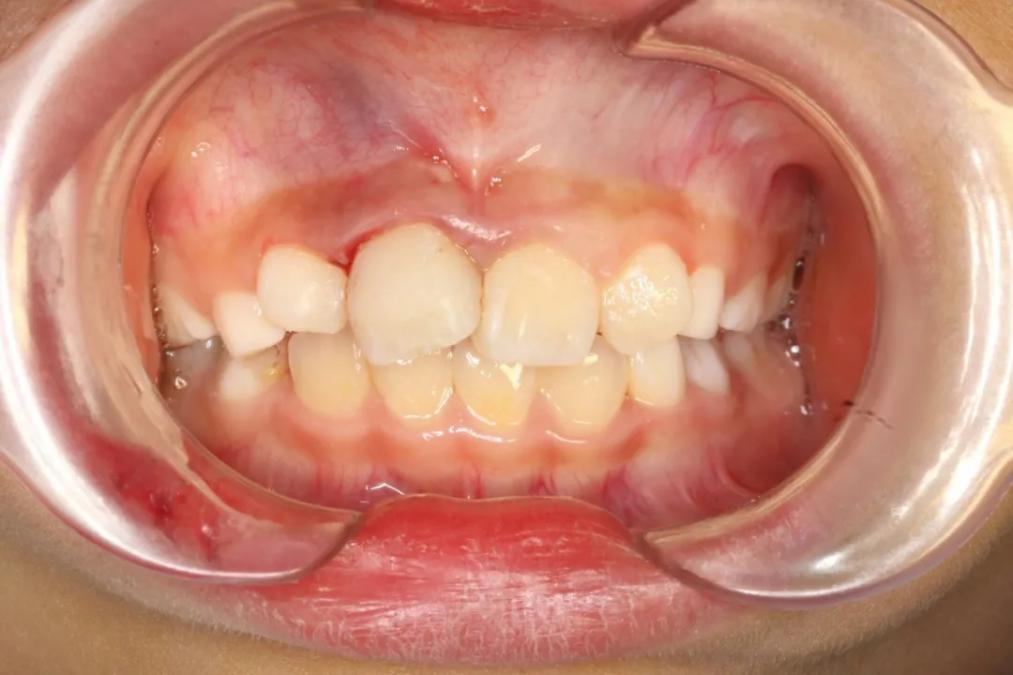

治疗后

结束治疗后,甜甜惊喜地发现牙齿又"长"回去了,几乎看不出摔过的痕迹,彻底放下了对只有"半截门牙"的担忧,还主动向医生阿姨道谢。

牙外伤的第二步处理断冠再接,考虑甜甜的前牙有点拥挤,如不及时处理两边的牙齿移位侵占断牙的空间,接断冠就困难了。因此,张丽文医生和急诊团队又开始了忙碌的断冠再接。年轻恒牙的活髓切断和断冠再接是很精细的治疗,从准备工作到结束,相当的耗时。等甜甜完成治疗,时间已经到了下午14时多。